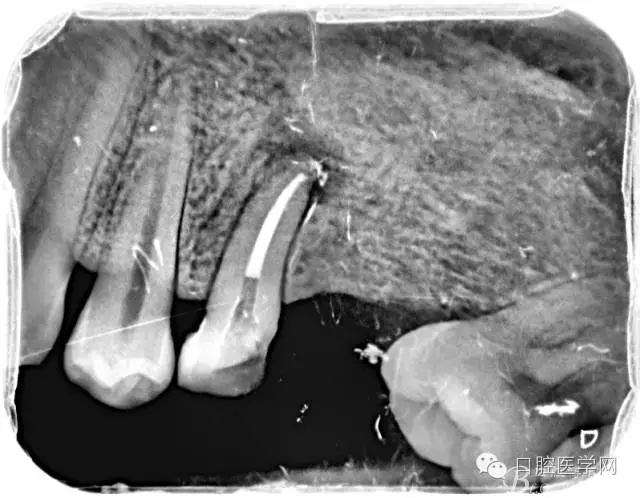

根管的解剖界限是从髓室根管入口到根尖部牙本质- 牙骨质交界处(生理性根尖孔) 。理想的根管充填应该是对生理性根尖孔冠方以上进行严密的三维封闭。临床上根据X线牙片判断根管充填的质量。牙片上充填材料与根管壁紧密接触一般被认为充填严密。关于充填止点,由于牙本质- 牙骨质界离根尖孔外表面平均距离为0. 5~0. 7 mm,同时相当多的根尖开口并不位于X线片的根尖处。因此临床上认为材料充填至距X线片牙根最尖端0. 5~1 mm (也有认为0. 5~2mm)为适填。

为达到更为理想的根充效果,研究人员和牙髓病医生一直在探索根管充填技术,并且发展出多种可供选择的方法。Ingle]将其归纳为3 类: ①“牙胶尖+封闭剂”式; ②“根尖1 /3充填”式; ③“注射或螺旋充填”式。目前临床广泛采用的主要是“牙胶尖+封闭剂”方式。按照充填压力的方向(侧向或垂直)不同和牙胶温度(冷或热)不同,根管充填有2 种基本技术:冷牙胶侧方加压充填和热牙胶垂直加压充填。现有的各种充填方法均是这2 种基本方法基础上的发展或改良。医生可根据方法的优缺点以及个人习惯选择使用。

6、封闭剂使用